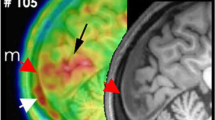

Interestingly, neuronal Panx1 activation as monitored by propidium influx was not limited to the cortex ipsilateral to CSD. It was also observed in the contralateral cortex and subcortical structures such as the dentate gyrus [10, 88] (Fig. 2B). Subsequent validation of this observation included the demonstration of widespread HMGB1 release from neurons and NF-ĸB activation in astrocytes in cortical and subcortical areas of both hemispheres [26]. These effects were less intense in the contralateral hemisphere. Importantly, these experimental observations conform with PET findings that revealed bi-hemispheric cortical as well as subcortical inflammatory tracer uptake in patients suffering from frequent migraine with aura attacks [19, 20] (Fig. 2A). The mechanisms underlying the spread of this phenomenon and its potential association with bilateral headaches following unilateral aura remain unclear. Notably, the significant propidium iodide uptake in dentate gyrus granular neurons, in contrast to neighboring CA sector pyramidal neurons, suggests a propagation via axonal volleys from the entorhinal cortex rather than gray matter or interstitium continuity. These volleys typically fire at the onset of CSD wave before depression of electrical activity [89]. The heightened excitatory firing, akin to observations during epileptiform discharges, has the potential to activate Panx1 channels due to the overactivation of NMDA receptors and rise in extracellular K+ [75, 90]. In support of this notion, when NMDA receptors were inhibited by locally applied MK801 to the cortex contralateral to the site where CSD was generated, HMGB1 release was suppressed in the contralateral (non-CSD) cortex, without any discernible impact on the CSD occurring on the ipsilateral side [26]. Likewise, in familial hemiplegic migraine type 1 mice exhibiting enhanced glutamate release due to a knock-in S218L missense mutation in α1A subunit of presynaptic CaV2 (but not in R192Q knock-in exhibiting less severe phenotype [26]), HMGB1 release in the contralateral cortex was increased [27].

CSD-induced inflammatory activity propagates through the brain, meninges, and skull. A. PET studies utilizing inflammation markers revealed bi-hemispheric cortical as well as subcortical inflammatory tracer uptake in patients suffering from frequent migraine with aura attacks. B. Consistent with clinical observations, Panx1 activity, monitored by propidium iodide (PI) influx to neurons (red fluorescence), was not confined to the cortex (Cx) ipsilateral to CSD but was also evident in the contralateral cortex and subcortical structures such as the dentate gyrus (DG) in the mouse brain. C. Simultaneous tracer uptake ([11C]PBR28) was observed in the affected occipital cortex responsible for generating the aura and the overlying dura, extending to the adjacent bone marrow. These findings suggest that myeloid cells may also contribute to inflammation in addition to the inflammatory mediators released from astrocyte endfeet and dural cells (D), thus underscoring the significance of sustained dural inflammation in migraine headache generation. Lym: lymphocyte, DC: dendritic cell, Mac: macrophage, Mono: monocyte, MC: mast cell. Reproduced from [10, 19, 91] with permission. Illustrations were created using BioRender.com and Servier Medical Art (http://www.servier.com).

Advancements in neuroimaging techniques are promising to be able to directly assess the presence of the mechanisms discussed above in migraine patients. Particularly encouraging is the detection of the meningeal uptake of the inflammatory tracer [11C]PBR28 over the occipital cortex, exhibiting parenchymal uptake in patients suffering from migraine with visual aura [20] (Fig. 2). [11C]PBR28 PET may also provide insight into the relationship between inflammatory signaling and headache in secondary headache disorders such as post-seizure headache. [11C]PBR28 exploits its high affinity against the 18 kDa translocator protein (TSPO) in the outer mitochondrial membrane, an inflammation-specific biomarker in activated glial cells. TSPO-PET imaging is increasingly being utilized for various clinical populations to disclose neuroinflammatory involvement. For example, in patients with chronic neurodegenerative disorders such as amyotrophic lateral sclerosis and Alzheimer’s disease, inflammatory glial activation in the central nervous system (CNS) has been demonstrated starting from the early stages [133, 134]. Despite inconsistent results with [11C]PBR28 [135], another TSPO ligand, [18F]FEPPA, showed a notable increase in glial uptake in patients with depression in relevant regions like the anterior cingulate cortex and hippocampus [136]. These discrepancies underscore the ongoing need for improved PET ligands, as TSPO signals can be confounded by variable binding affinities depending on TSPO gene polymorphisms, issues with TSPO binding specificity, and their in vivo metabolic profiles. Next-generation tracers with enhanced TSPO binding features are in active development [137]. If successful, these improved tracers can play a pivotal role in resolving some of the controversies surrounding the role of meningeal neurogenic inflammation and parenchymal inflammatory signaling in migraine. Moreover, it is worth noting that, inflammatory glial activation in the brain and the spinal cord has also been shown with [11C]PBR28 PET in chronic pain conditions other than migraine, such as chronic low back pain [138, 139] and fibromyalgia [135], suggesting a shared neuroinflammatory element across a heterogeneity of pain-related conditions [140].